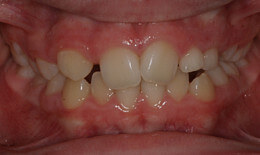

• Small upper jaw with crossbites